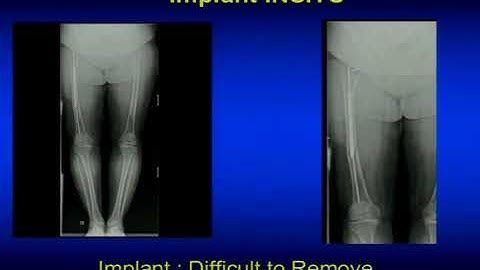

TKR using Computer Navigation – Best Explained by Dr. Vivek Mahajan of ISIC, New Delhi